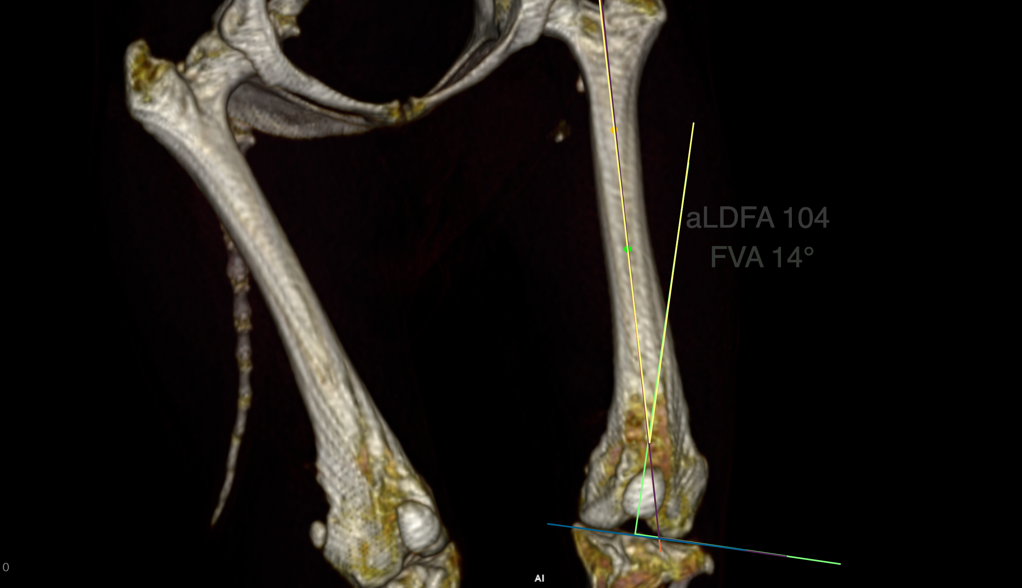

Quando necessario, il veterinario utilizza esami di imaging come le radiografie, utili per valutare ossa e articolazioni, oppure tecniche più avanzate come ecografie, TAC o risonanza magnetica, che consentono di studiare in modo più dettagliato tessuti molli, legamenti e strutture interne.